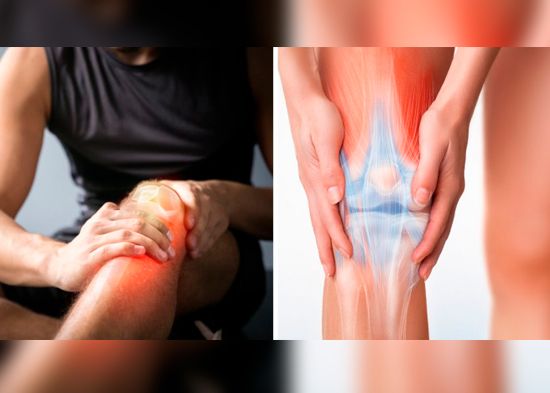

Por qué hay dolor de rodilla y cómo aliviarlo con ejercicio

Luego de hacer mucho ejercicio o dar un mal paso, lo más común es sufrir una lesión en la pierna. Ya sea que se lastime el tobillo, el muslo o la rodilla. Si el dolor persiste en la rodilla, lo relacionamos con la edad. Sin embargo, ese dolor podría tener otra causa. Averigua por qué hay dolor de rodilla y algunos consejos para aliviar la molestia.